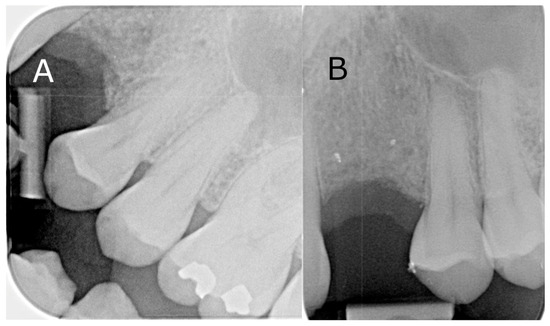

A 49-year-old male patient presented requesting restorative options for a missing 23. A dental implant was proposed as a treatment option, and the patient consented to proceed. During screening with OPG and CBCT, a submerged radiopaque GP was observed. The GP intersected the ideal implant position (Figure 5A). It was decided that it would be removed utilising a surgical guide to minimise cortical plate loss for bone preservation prior to implant placement. The treatment plan was discussed with the patient, and informed consent was obtained. Local anaesthesia with 4% articaine containing 1:100,000 adrenaline was administered via buccal, palatal, and mid-crestal infiltrations. A mid-crestal incision and vertical relieving incisions were performed. A full thickness periosteal flap was raised at the left canine region to expose the alveolar ridge. The surgical guide was placed over the exposed ridge to indicate the position of the retained GP and subsequent corticotomy. A Ø 1.4 mm small round bur was then inserted through the surgical guide channel to remove the cortical plate to reveal the GP (Figure 5B). The GP was removed with a small spoon excavator, and a periapical radiograph was taken to ensure the complete removal of restorative debris (Figure 5C). The width of the osteotomy site was 3 mm at the apical end and 2 mm at the coronal end (Figure 5D). The Bio-Gide membrane (Geislitch) was placed over the osteotomy site to prevent soft tissue growth into the defect and enable fibroblast attachment for the formation of new bone tissues and blood vessels in the defect. No bone substitute material was used. The flap was repositioned and secured with six simple interrupted sutures using PROLENE suture 5-0 (Ethicon). The surgical site was reviewed at 6 and 12 months post-operatively, with intraoral radiographs confirming the complete removal of the GP (Figure 6).

Figure 6. Intraoral radiographs of the surgical site from the precision osteotomy: (A) 6-month follow-up; (B) 12-month follow-up.